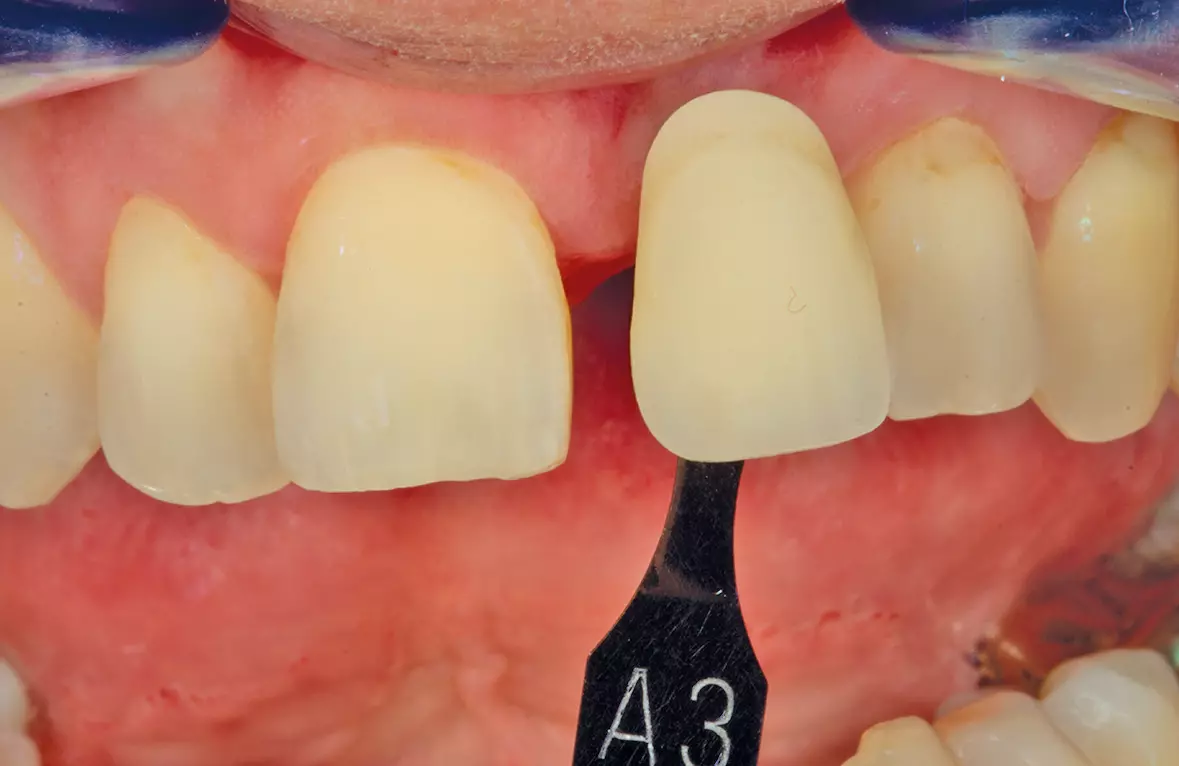

Nun konnte die Reaktion der Gingiva abgewartet, eine genaue Zahnfarbkontrolle erfolgen sowie eventuelle Formkorrekturen analysiert und in die definitive Versorgung übernommen werden. Für die Umsetzung wurde das Modell eingescannt. Digital wurde jetzt die endgültige Krone konstruiert. Dabei kam das Ceramill CAD/CAM-System von Amann Girrbach GmbH zum Einsatz. Im Ceramill Map Scanner wurden die erforderlichen Modelle eingescannt bzw. digitalisiert (Abb. 19). Da die Zahnform schon vorgegeben war, konnte man über einen Situationsscan die spätere Form im Scan erfassen und musste danach lediglich die zu verblendende Fläche reduzieren. In der Ceramill Mind Konstruktionssoftware wurden alle weiteren Schritte in der Folge abgearbeitet und die Krone schließlich in der Ceramill Motion Fräs- und Schleifeinheit aus Zirkon (Ceramill ZI) gefräst. Wichtig war hierbei, dass der Schraubenkanal in Zirkon gefasst blieb (Abb. 20 und 21).

Hierdurch war beim Einschrauben der Implantatkrone eine gute Führung vorhanden und die Verblen dung konnte nicht versehentlich durch den Schraubendreher beschädigt werden. Für die genaue Farbwahl wurden die Zähne mit einem PolarEyes-Filter fotografiert, um die genauen Strukturen des Zahnes und seiner einzelnen Schichten zu analysieren und später in Keramik umzusetzen (Abb. 22-24).